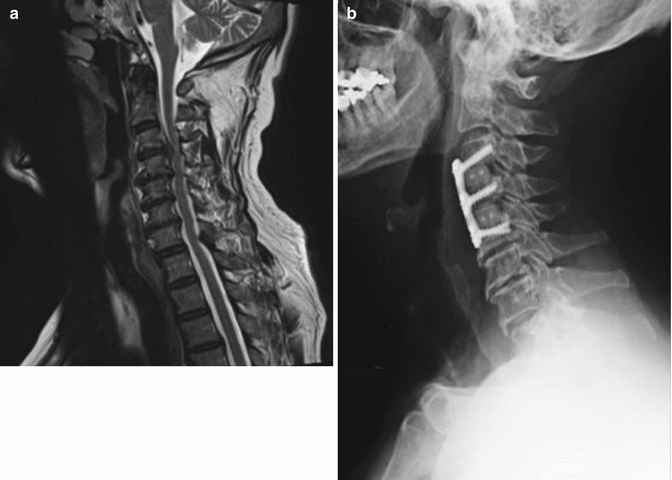

Cervical surgery to decrease radiated pain or decreased strength in the upper upper limb has a success rate that according to the literature can be around 80 to 90%. Fusion was assessed on dynamic radiographs. Previous cervical spine fusion surgery.

The average number of days to revision surgery was 750.6±570.3 days. Regardless of whether the procedure is anterior or posterior, studies show that neck surgery to treat arm pain from cervical radiculopathy has an 80% to 90% success rate. Patients failing to respond have a high success rate for surgery, with rates of arm pain relief in many studies ranging from 85% to 95%.

The overall fusion rate for multilevel acdf was 69.6%, the fusion rate was 86.7% for 2.